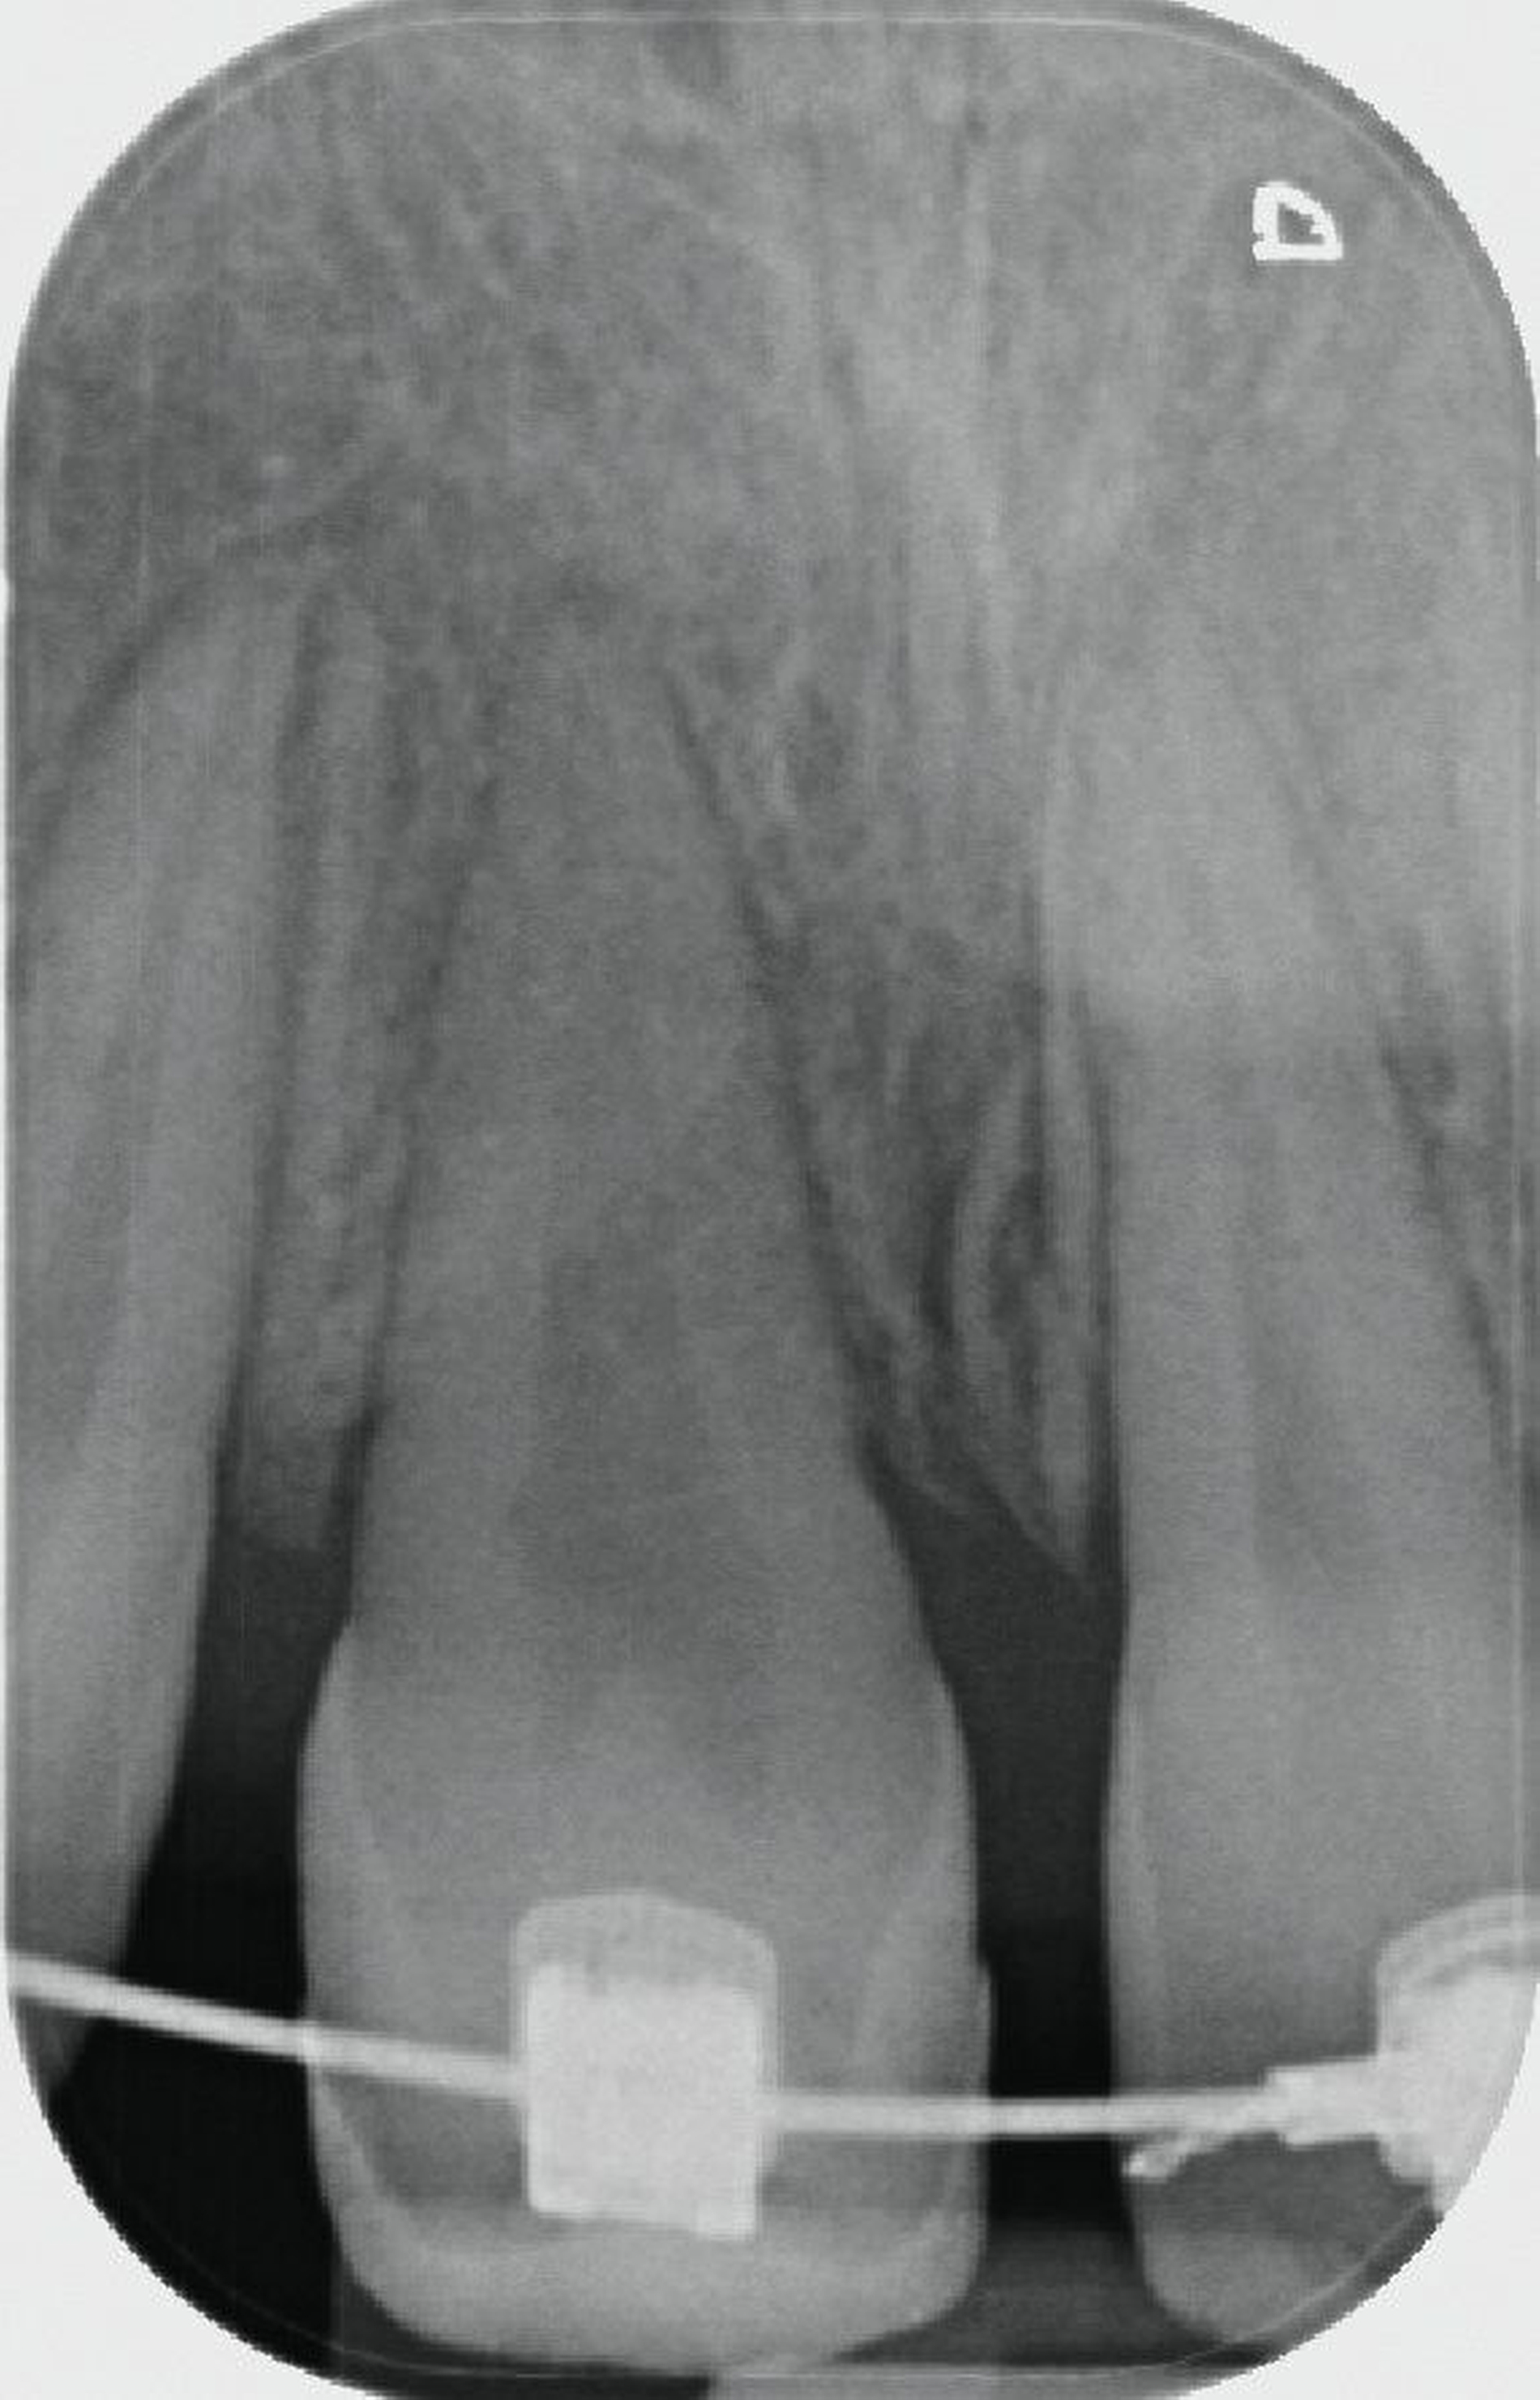

Durch die 90-Grad-Rotation des Transplantats stellt sich der Zahn anatomisch in der okklusalen Ansicht (Abbildung 7a) in der Sagittalen nahezu so breit dar wie der Nachbarzahn 21. Der adhäsive Frontzahnaufbau erfolgte drei Monate postoperativ noch unter der kieferorthopädischen Bracketierung. Die Weichgewebshöhe am Transplantat 11 ist durch die kieferorthopädische Extrusion ebenfalls als isogingival zum Nachbarzahn 21 zu erkennen. Der Klopfschall am TX-Zahn 11 war normoton und wies keine Ankylose auf. Die Sensibilitätsprüfung des Zahnes war positiv. Die Obliteration der Zahnwurzel weist auf eine vitale Reaktion des Pulpagewebes hin, wie man sie auch bei erfolgreich replantierten jugendlichen Zähnen beobachtet.

Nach dem Erreichen der isogingivalen Höhe des Zahnfleischrandes durch die kieferorthopädische Extrusionstherapie konnte die Zahnkrone des Transplantats zeitnah ästhetisch aufgebaut werden (Abbildung 7c). Die Entscheidung, auf welche Art die Lücke an der Entnahmestelle des Transplantats geschlossen wird, obliegt den Kollegen der Kieferorthopädie. Die Überlebens- und Erfolgsraten der Prämolaren-Transplantation sind heutzutage so gut, dass die Methode in jedem Fall den Patienten empfohlen werden kann. In einer aktuellen Studie berichten Louropoulou et al. an 910 in die Oberkieferfront transplantierten Prämolaren, dass die 10-Jahres-Überlebens- und -Erfolgsraten beim jugendlichen Patienten 99,8 Prozent betragen [Louropoulou et al., 2023]. Insofern sollte diese chirurgische Methode im Fall eines nicht erhaltungswürdigen Frontzahns im Jugendalter unbedingt mit in die differenzialtherapeutischen Überlegungen einbezogen werden [Andreasen et al., 2009; Louropoulou et al., 2023].